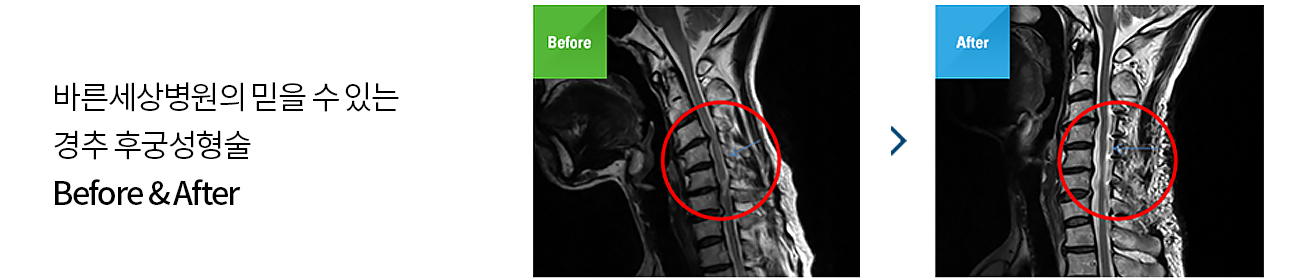

후궁이라는 뼈는 목뼈의 척수신경이 지나가는 부위의 뚜껑에 해당하는 뼈입니다. 이 부위를 열어 눌린 척수신경을 풀어줍니다.

뚜껑을 여는 수술작업이 후궁의 모양을 정상적으로 성형한다 하여 후궁성형술이라고 합니다.

후종인대 골화증이 심해 경추 척수증으로 진단될 경우 경추 후궁성형술로 치료하게 됩니다.